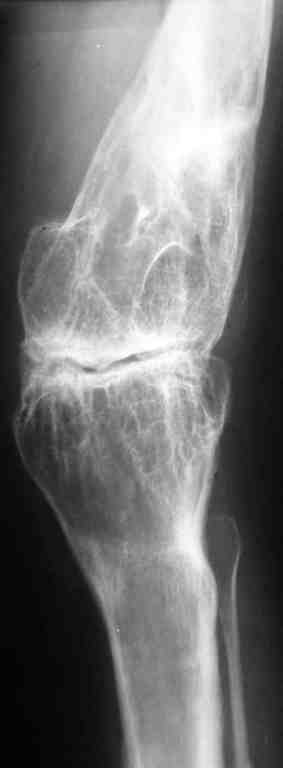

Уважаемые коллеги! К мне обратилась моя бывшая пациентка, 22 лет, с просьбой об эндопротезировнии коленного сустава. От артродеза категорически отказывается.DS: Врождённая аномалия развития левой нижней конечности. Состояние после удлинения бедра и голени (около 45 см). Варусная деформация шейки лев. бедра. Лев. коксартроз II ст. Лев. гонартроз III ст. Разгибательная контрактура лев. коленного сустава. Парез малоберцового нерва слева. Укорочение лев. н/конечности 1,5 см. Жалобы: на боли и нарушение функции в лев. коленном суставе.St. localis: ходит в брейсе с опорой на 1 трость. Относительная длина ног S – 1,5 см. Движения в лев. т/б суставе: сгиб. 70, разг. 180, привед. 60, отвед. 110, вн. рот. 20, нар. рот. 10; в лев. к/сус. пассивно: сгибание 0, разг. - 180+ 30; активно на переразгибание и из положения переразгибание на сгибание 2балла. Под нагрузкой вальгусно-рекурвационная деформация: клиничски на val. – 15-20, rec. - 30. Движения в лев. голеностопном суставе (акт./пас.): тыл. фл. 0/90, под. фл. 170, отвед. 10/15, прив. 25. Функция в других суставах не нарушена.Предполагаю, что наиболее лучшим вариантом будет двух этапное протезирование. На первом этапе – устранить антекурвацию на бедре аппаратом Илизарова; вторым этапом – протезирование – заднее-стабилизирующим протезом фирмы «Zimmer», т.к. маленькие размеры бедренной и большеберцовой костей.Возможны ли другие варианты лечения? Возможно ли одно этапное протезирование?Целесообразно ли в данном случае протезирование? Может быть не стоит идти «на поводу» у пациентки.Буду очень признателен всем, кто откликнется на мою просьбу.С уважением Игорь Атманский.

В настоящее время нет возможности сделать осевые снимки всей конечности. Это всё чем я раполагаю на сегодняшний день.

Трудно понять общую картину по "короткому" снимку в одной проекции. Желательно было бы увидеть нормальный снимок в двух проекциях, оптимально еще и снимок, захватывающий всю ось конечности от тазобедренного до голеностопного сустава.

Учитывая неоднозначность данного случая, такой снимок все равно надо делать.

Что касается самых общих соображений, то вызывает сомнения состоятельность боковых связок.